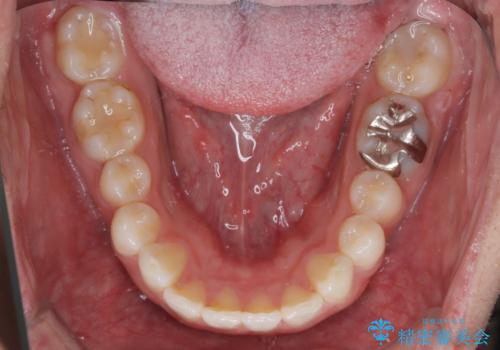

- 前歯の隙間と口元を主訴に来院されました。

インビザラインにて治療を行いきれいな歯並びをつくることができました。

奥歯の噛み合わせもきちんと仕上げることができました。